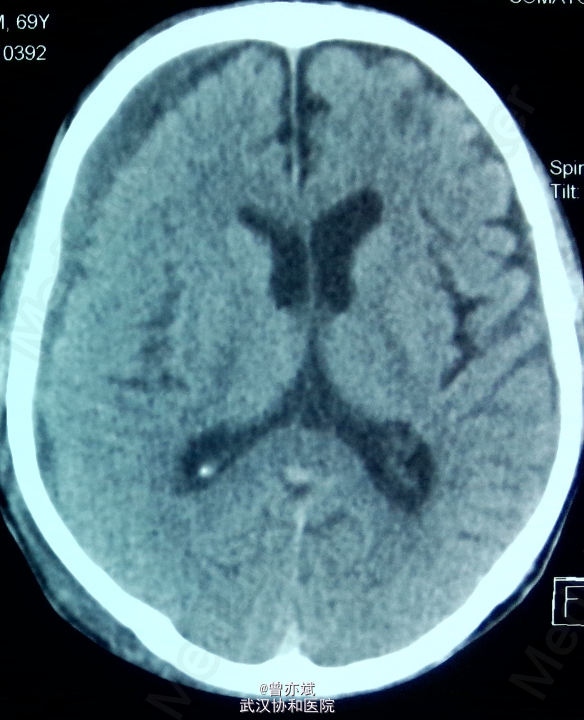

5天后的CT如下:血肿较前稍减少,密度稍减低 摔倒后当时无明显的症状,之后出现慢性硬膜下血肿,特别是在老年人中更易出现,摔倒后弱头部着地,应行CT检查。